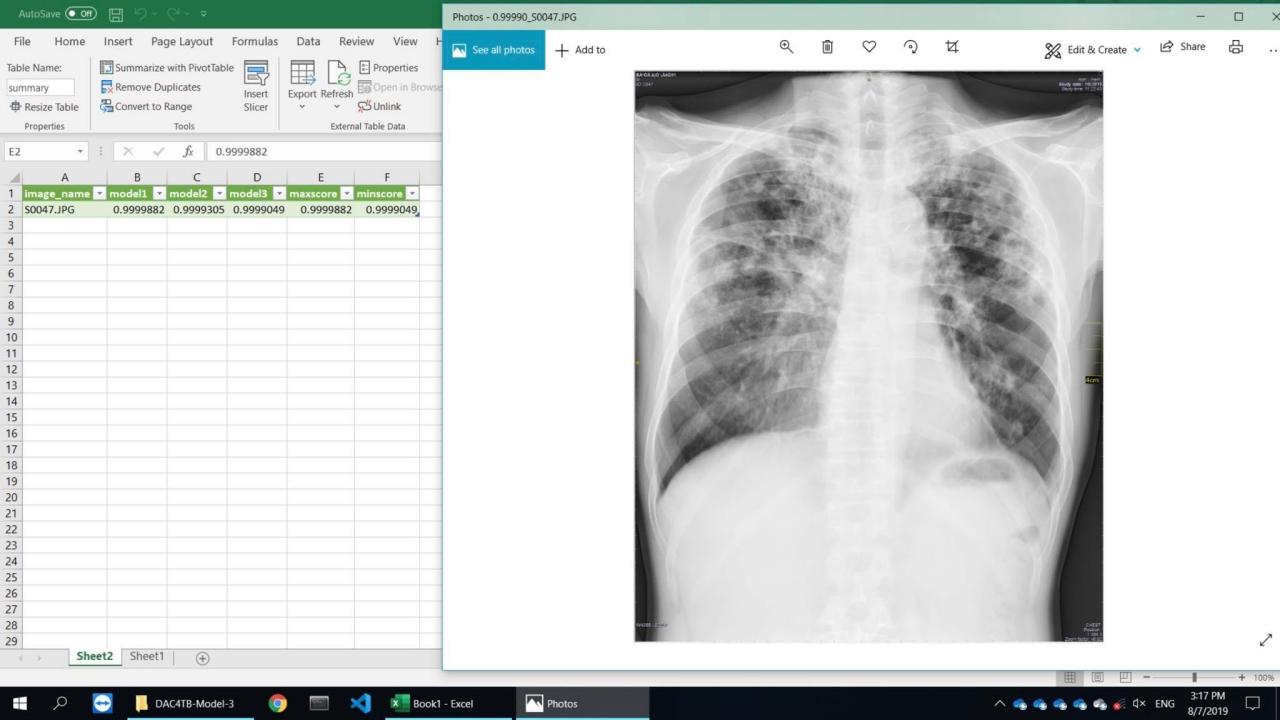

5. เทคโนโลยี AI จะประมวลผลออกมา โดยเป็นลักษณะของตัวเลข 0 ถึง 1 เช่น 0.56, 0.99 เป็นต้น (ประมวลผลจากรูปที่มีข้อมูลเป็นพิกเซล เปลี่ยนมาเป็นตัวเลข)

6. เทคโนโลยี AI จัดเรียงลำดับผู้ที่มีความเสี่ยงติดเชื้อวัณโรคจากมากไปหาน้อย

7. ผู้ที่มีผลคะแนนลำดับต้นๆ ถือว่า มีความน่าสงสัยที่จะติดเชื้อวัณโรค

8. แพทย์จะรู้ได้ทันทีว่า นักโทษรายใดมีความเสี่ยง และจะนำไปสู่ขั้นตอนการตรวจเสมหะ เพื่อวินิจฉัยโรคได้อย่างรวดเร็ว

เทคโนโลยี AI สามารถอ่านผลหลังจากที่ขึ้นไปเอกซเรย์บนรถได้ทันที เมื่อทราบผลคะแนนเป็นที่เรียบร้อยแล้ว เจ้าหน้าที่ผู้เกี่ยวข้องก็สามารถแจ้งผู้รับบริการได้ ณ เวลานั้นเลย หากผลวินิจฉัยวัณโรคออกมาแล้วพบว่า มีความเสี่ยงจะติดเชื้อ แพทย์ก็สามารถนำบุคคลท่านนั้นๆ ไปตรวจเสมหะ เพื่อวินิจฉัยวัณโรค และทำการรักษาได้อย่างรวดเร็ว” ผศ.ดร.นพ.กฤษณ์ พยายามกล่าวเรื่องเทคโนโลยีและเรื่องสาธารณสุขให้เข้าใจง่ายที่สุด

เทคโนโลยีโปรแกรมปัญญาประดิษฐ์ หรือ AI